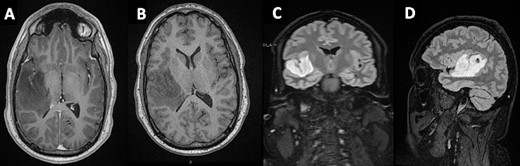

In light of the persistent synchronous symptoms, imaging was obtained. An MRI head revealed a non-enhancing, T1-hyperintense lesion within the HG in the right cerebral hemisphere (Fig. 1), extending into the insular cortex. A Stealth guided burrhole biopsy of the right temporal lobe was performed. Pathological analysis revealed a Grade II diffuse astrocytoma.

Mass lesion occupying the HG on the right temporal gyrus on (A) axial post-contrast T1 - (B) axial non-contrast T1- (C + D) T1-weighted sagittal and coronal FLAIR MRIs, respectively.